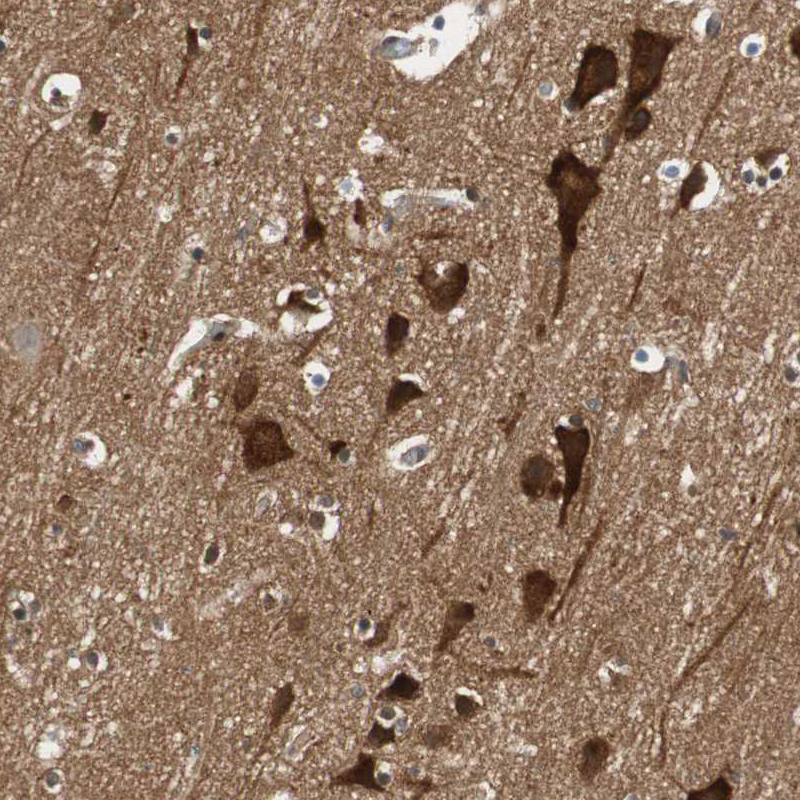

Immunohistochemistry analysis in human cerebral cortex and skeletal muscle tissues using HPA005750 antibody. Corresponding WASL RNA-seq data are presented for the same tissues.